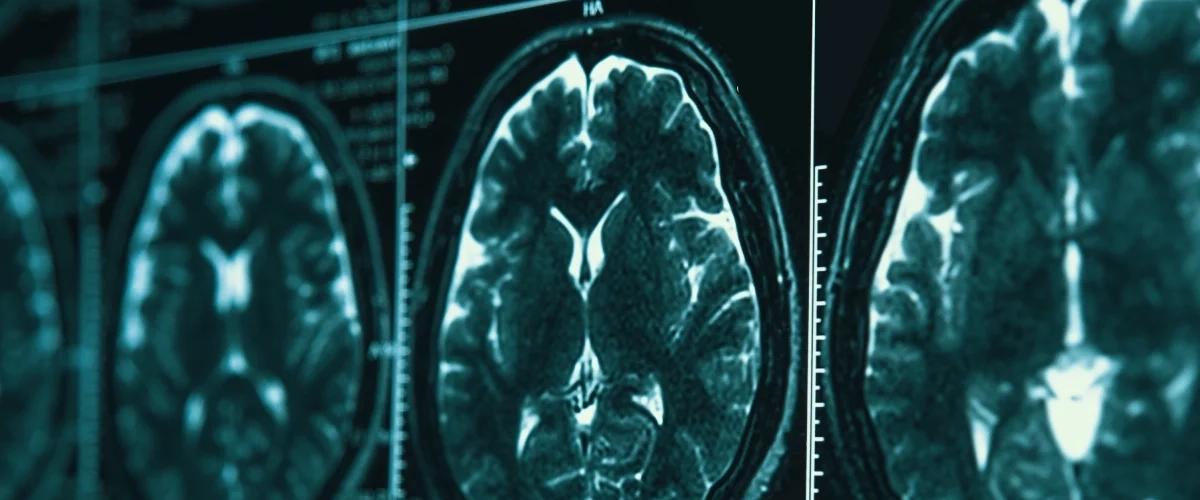

Визуализация дает уникальные прямые сведения о структурном старении мозга, которые нельзя получить из показателей крови и других молекулярных биомаркеров. Например, к основным признакам старения относится толщина коры головного мозга, контролирующая речь и мышление, а также объем серого вещества. Оценивая эти и другие характеристики, ученые решили создать инструмент для выявления темпов старения мозга по МРТ. Результаты опубликованы в Nature.

Результатом стали новые «часы старения», которые оказались информативными при проверке результатов на выборке из почти 45 тыс. сканирований. Например, ускоренные показатели старения мозга в возрасте 72 лет были связаны с наиболее высокими рисками развития деменции в течение следующих 16 лет.

Пока авторы еще совершенствуют алгоритм, но видят большие перспективы нового ИИ для клинического применения. В будущем простая МРТ головного мозга может стать важным инструментом скрининга для пожилых и людей из группы высокого риска деменции.